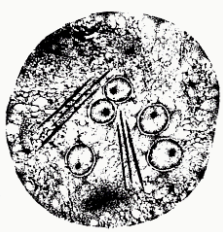

Cryptosporidium spp. (mature oocyst)